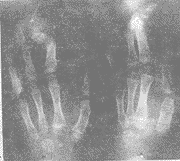

患儿,男,8岁,1990年10月出生,生后发现左手及双足均为4指(趾),且左手3、4指并指,右足内翻畸形。1999年6月来我院就诊。以“左手示指缺如并3、4指并指畸形”入院。检查:发育良好,营养中等,神志清楚,智力正常。头颅及五官正常,心、肺、腹无异常,除左手及双足外,脊柱四肢无畸形,功能正常。左手第2指全指缺如,第3、4指并指。伸屈尚好但肌力Ⅳ级,余指正常。双足第2趾缺如,余趾活动正常。右足内翻畸形,外翻不能,腓骨长短肌肌力0级。X线片示:左手示指掌骨指骨缺如,第3、4指末节骨并联(见图1)。双足第2楔骨及第2跖骨、趾骨缺如(见图2)。右足呈内翻畸形(见图3)。

图1 左手X线片